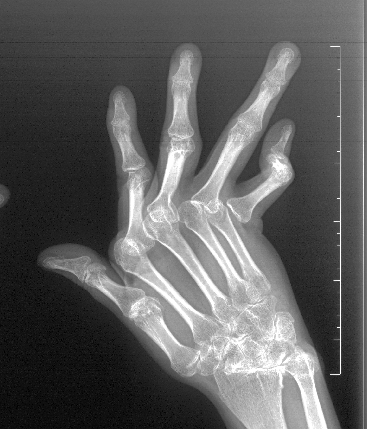

经过规范系统治疗,李女士的症状有所缓解,但疾病对她的“考验”才刚刚拉开帷幕。之后,由于间歇性停药,她的病情反复发作,关节肿痛如影随形。更令人揪心的是,双手关节开始变形,掌指关节半脱位、手指向尺侧偏斜,原本灵活的指尖逐渐变成了“鹅颈样畸形”。严重的关节畸形让她不得不放弃工作,生活被无助与自卑层层包裹。

一方面,畸形复杂且差异大。患者可能同时存在“纽扣样畸形”“鹅颈样畸形”“尺偏畸形”等多种问题,成品假体无法匹配。另一方面,关节微环境复杂。长期炎症导致滑膜炎、肌腱损伤,关节周围免疫微环境复杂,给假体植入和稳定带来巨大挑战。此外,传统假体缺陷明显。临床使用的硅胶假体普遍存在硬度不足、易松动等问题,甚至可能引发“硅胶假体性滑膜炎”,长期效果差强人意。而且,围手术期风险高。患者因长期服用免疫抑制剂,如何平衡炎症控制与手术安全,是必须攻克的难关。